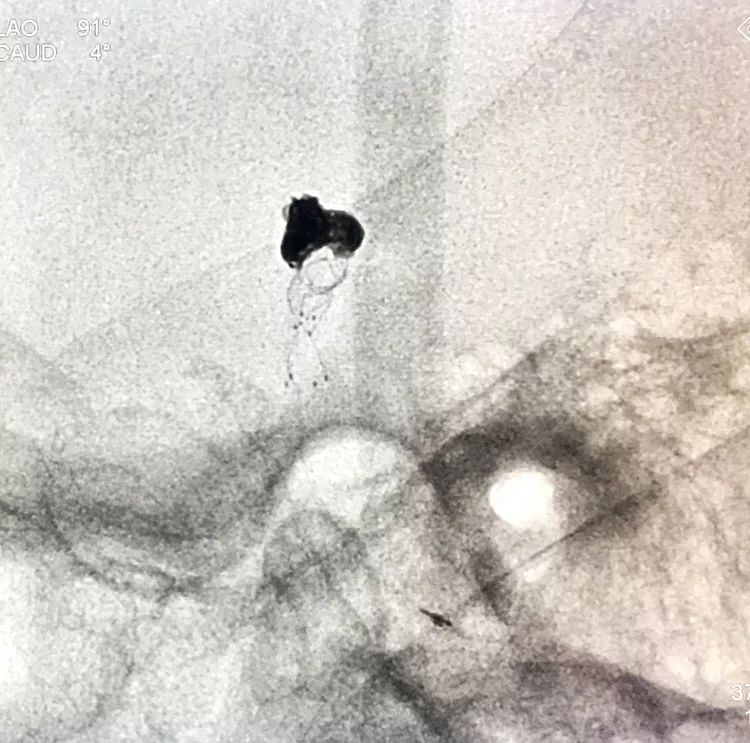

换用一根新的Echelon10微导管,头端塑成C型,以Arvigo14微导丝引导(先前的Sychro14微导丝的头端已经有损了),经LVIS支架内部接近瘤腔后部的死腔,但微导丝可以进入死腔,微导管头死活钻不进去,被LVIS支架的网丝挡住去路,怎么办?那就隔着渔网袜挠痒!

微导管头顶在支架网眼处,投送一枚1.5-2的小圈,一开始弹簧圈走行入载瘤动脉(支架)内,用扭具调整弹簧圈头端的行进方向,并随之微调微导管头的方向和张力,圈终于成功钻入死腔!

再投入一枚1.5-3的小圈

继续钻入一枚1.5-2的小圈

嗯,完美收官!